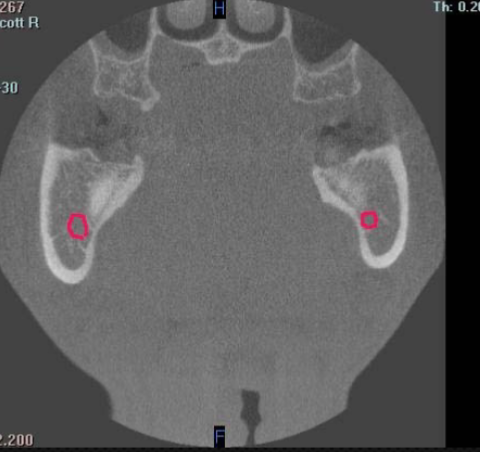

mandibular condyle

identify structure